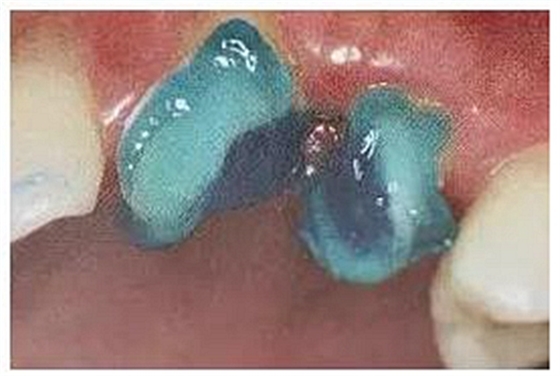

13.不規(guī)則根管的纖維樁粘接

普通纖維樁對圓形截面的根管適合性較好,面對不規(guī)則時(shí)(橢圓形、喇叭形等)根管適應(yīng)性差,難以取得好粘接和修復(fù)效果。

(輔樁的運(yùn)用)

輔樁的運(yùn)用可改善這些適應(yīng)性的問題。

(ELLIPSON 技術(shù))

(超聲預(yù)備根管完成)

ELLIPSON

技術(shù),采用超聲預(yù)備鉆對扁圓形根管進(jìn)行直接預(yù)備,改善了樁核根管的適應(yīng)性。有效的保存了根管牙體組織,從而增強(qiáng)了粘接面積,,減少樹脂水門汀的厚度,提高根管內(nèi)纖維樁的粘接強(qiáng)度。

(插入橢圓形纖維樁)